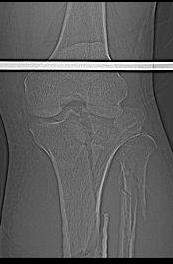

Пациенту сделали КТ - ухитрились сделать на шине Белера (не давал положить прямую ногу) - срезали передний отдел. Планируется на пятницу (24.12) на операцию - синтез  длинной мыщелковой LCP-пластиной Synthes :). Отек ближе к слову умеренный (окружность голени +4 см по сравнению со здоровой). КТ и снимок на вытяжении прилагаются.